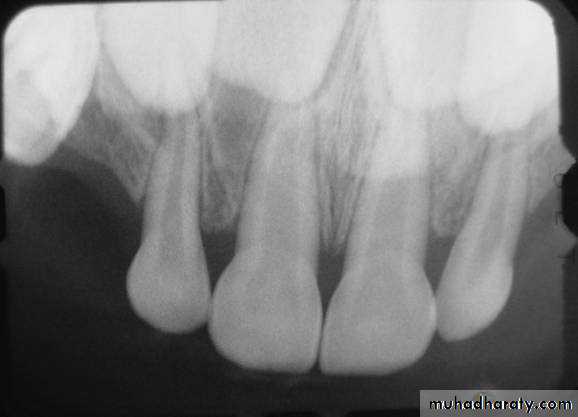

Roots of primary teeth

Roots of anterior teeth are narrower mesiodistally

Posterior teeth have longer and more slender roots in relation to crown size

Molar roots flare more as they approach the apex

Apical foramina may be larger and accessory canals often larger and more numerous

Roots of primary molars:

are longer and more slender in relation to crown size

are more flared as they approach the apex in order to accommodate the developing permanent tooth buds